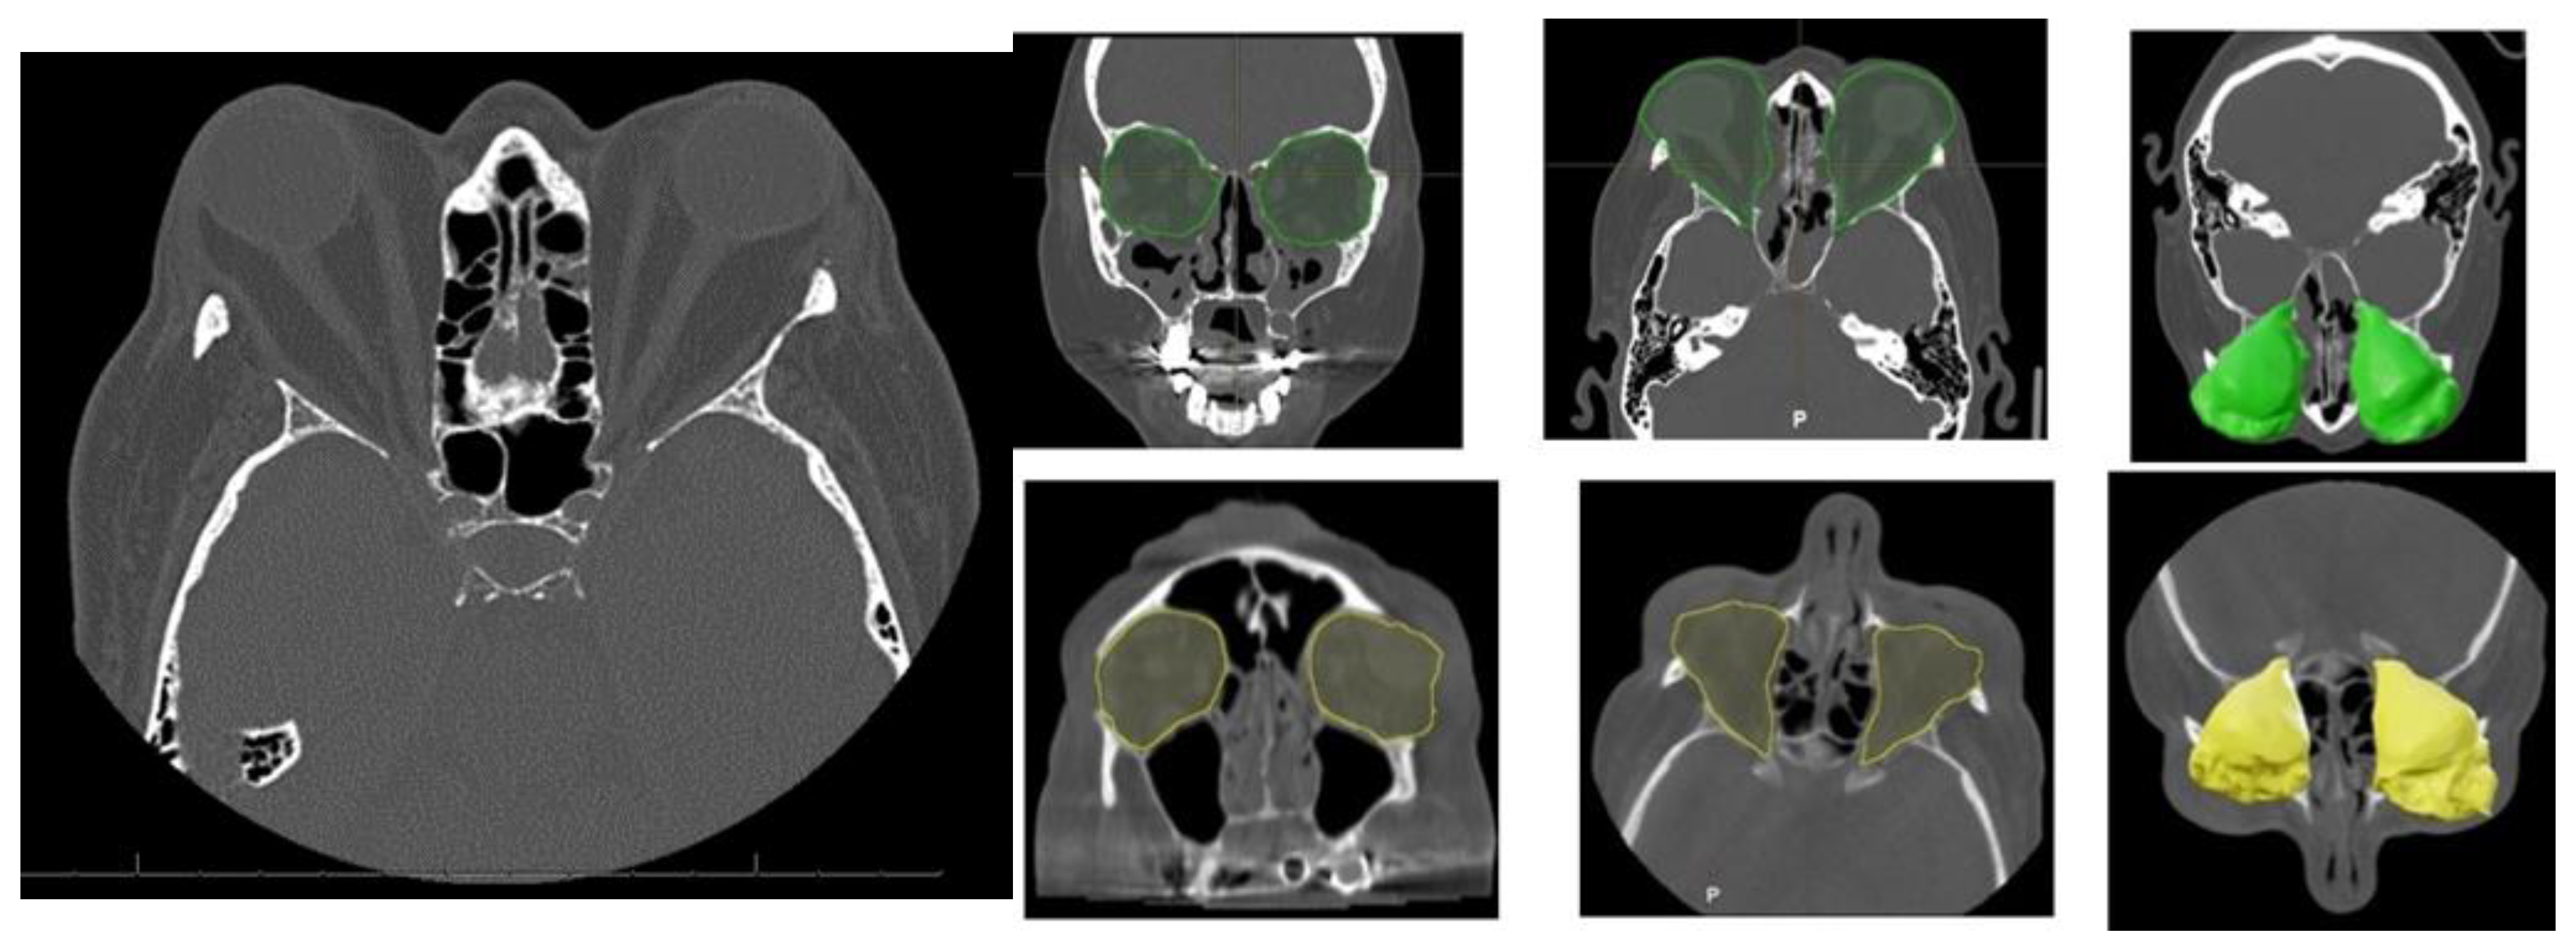

Orbital Computed Tomography (CT) imaging (Figure 2) revealed bilateral exophthalmos associated with substantial hypertrophy of intra- and extraconal orbital fat, alongside extraocular muscle enlargement. The superior recti muscles were primarily affected, with minor involvement of the right medial rectus and inferior recti muscles.

Figure 2.

Characteristic orbital findings in Graves’ orbitopathy. Axial and coronal CT images showing hallmark features of Graves’ orbitopathy, including bilateral enlargement of extraocular muscles (notably the inferior and medial rectus), with sparing of the tendinous insertions. Increased orbital fat volume and anterior displacement of the globe (proptosis) are also visible. These changes contribute to compressive effects on the optic nerve and are commonly used for diagnostic and preoperative planning purposes. Preoperative intra-orbital volume shown in green; postoperative volume in yellow.